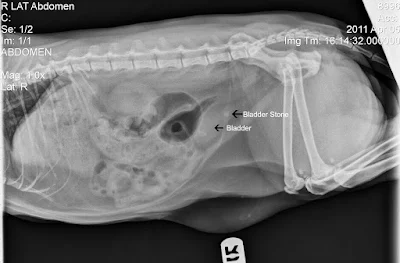

Radyogram; 3 boyutlu bir yapının 2 boyutlu bir görüntüsüdür. Filmin incelenmesi ile;

a. Organizmanın dış yapısı ve şekli

b. İncelenen organın iç yapısı ve diğer detaylar

c. Bölgenin radyolojik yoğunluğundaki değişimler (kalsifikasyonda yoğunluk artar, gaz oluşumunda azalır) araştırılır .

Dokuların X Işınlarını Absorbe Etme Özelliği

Radyografisi alınacak cisim hava ihtiva ediyorsa röntgen filmi üzerinde Radyolusent,

Yağlı dokular, ürik asit bazları, Azalan Radyolusent,

Kas, kan, kıkırdak, bağdoku, epitelyum ve kolesterol taşları, Orta Radyolusent,

Kemik dokusu Azalan Radyodens – Radyopak,

Ağır metaller (BaSO4), Çok Radyodens-Radyopak görüntü